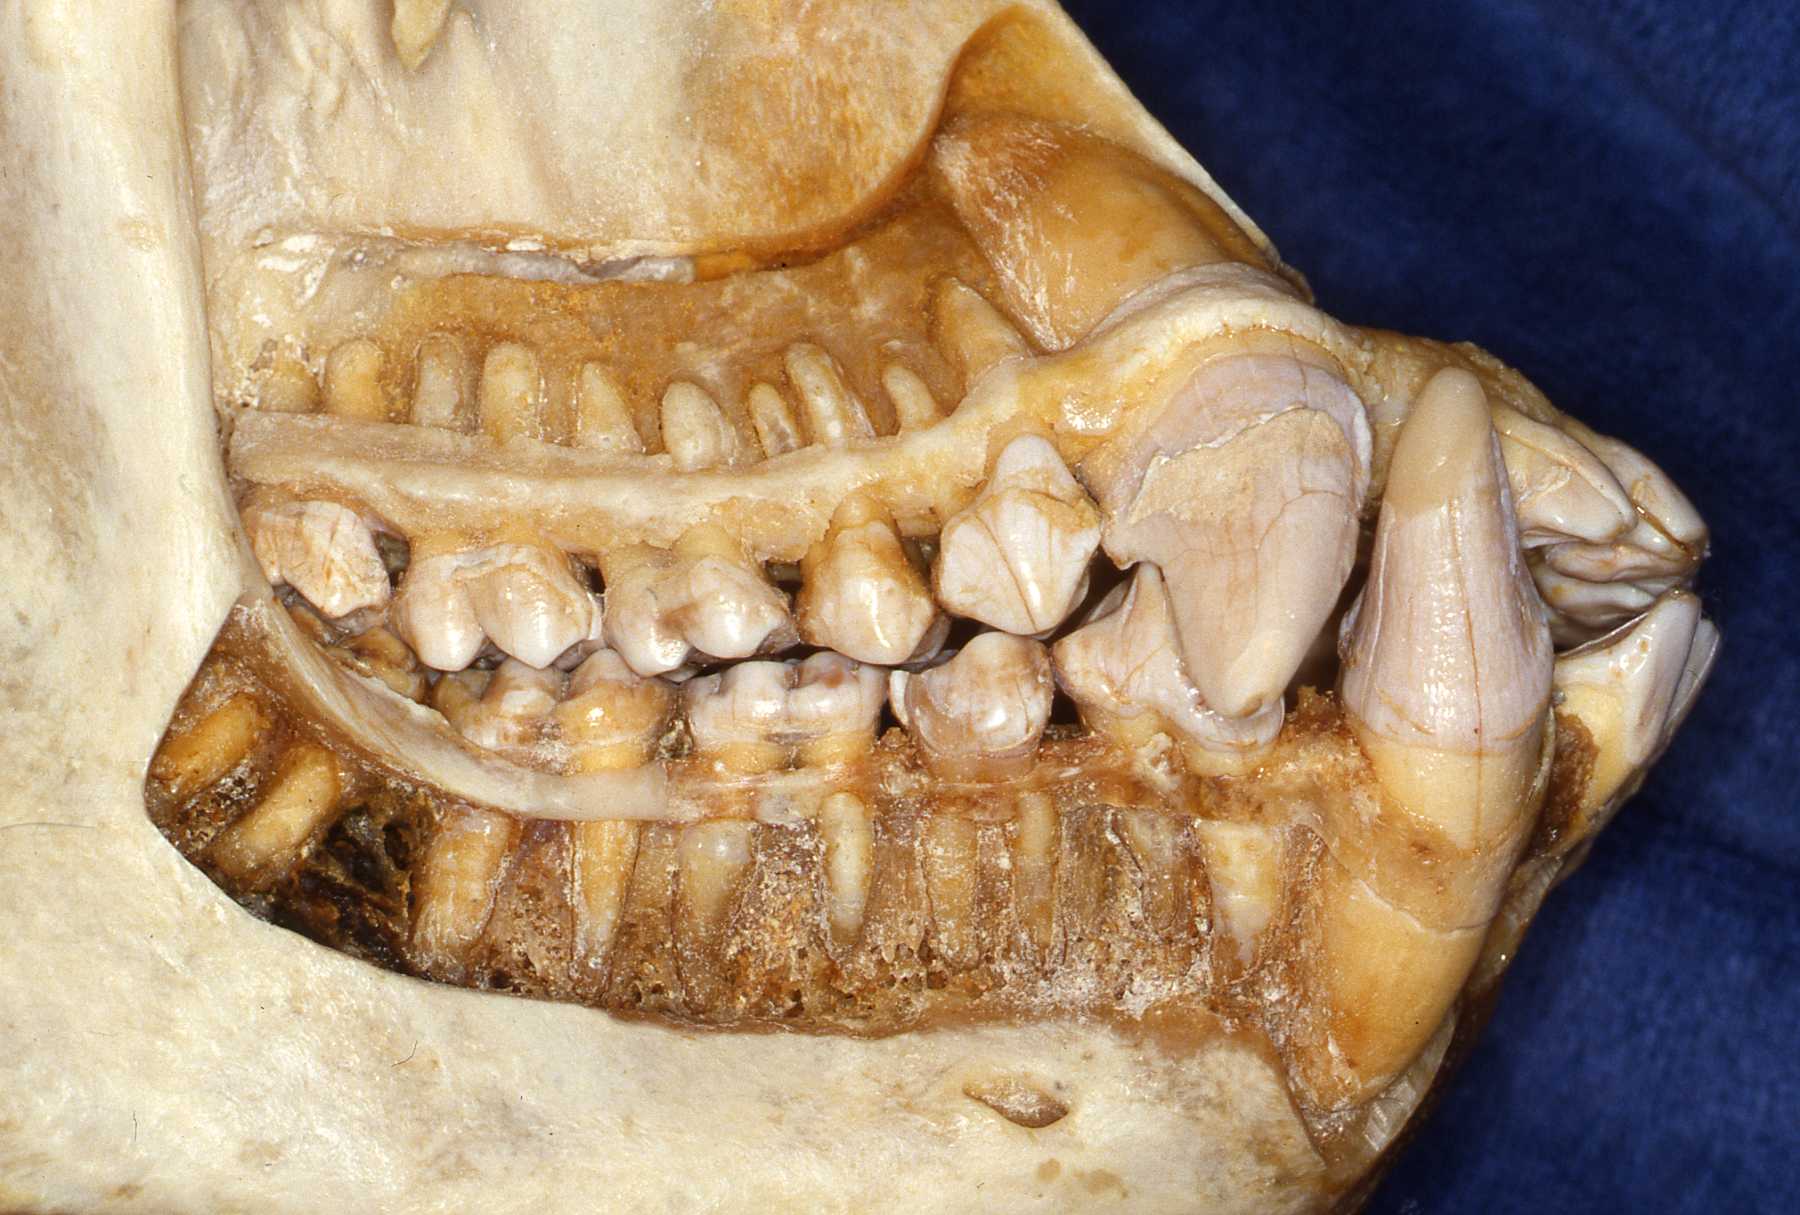

Use references such as those listed on this site. Radiographs of the particular species are very helpful. Skull and teeth collections are the optimum for preparation. I have encouraged accumulating a collection at our zoo and we have established an archive from animals that died at Milwaukee County Zoo. Over the years I established a relationship with the Milwaukee County Museum and the Zoological Museum at the University of Wisconsin, Madison. They receive the carcasses of our animals after pathologists evaluate them. Then the animals' skeletons are added to their or our collection.

The apes will have the same number of teeth as humans. That is 20 primary teeth and 32 permanent teeth. The same is true for the old world monkeys. Some new world monkeys have three premolars per quadrant. Other primate groups have various dental formulae. The primate teeth are anelodont with very few exceptions (aye-aye for example). There are also variations in numbers of roots. Therefore, again, preoperative radiographs should always be reviewed prior to extraction or endodontic procedures. The root apices usually have single orifices with a small percentage having auxiliary canal openings or perhaps two apical openings as often found in humans.

We have also encountered anatomic variations and anomalies in several species such as supernumerary teeth and impactions. Again, knowing the "normal" situation and always taking preoperative radiographs is necessary to recognize such situations. Such variations and anomalies do not necessarily warrant treatment unless they are causing or will very likely lead to pathosis.

Primate Dental Anomalies